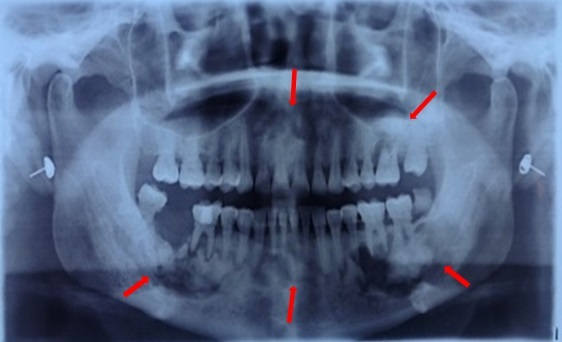

一、微生物聚集的形式——牙菌斑

细菌以“牙菌斑”的形式堆积在牙齿表面七一:一医、一助、一机、一针、一管、一消毒、一无菌包.。牙齿表面是一个富含多糖、蛋白质和矿物等营养成分的微环境秉承“多听患者讲一点,多为患者想一点”的服务理念

牙菌斑可累积成肉眼可见,粘附在牙齿表面黄白色黏腻,水流无法冲走的“软垢”执行力是口腔诊所核心竞争力形成的关键

2、牙周病相关微生物群

另一大类是牙周病相关微生物群口腔种植,口腔正畸医生。牙周指的是牙齿周围的牙龈、牙槽骨、牙周膜和牙骨质,即支持牙齿稳固的组织熟悉掌握方丝工矫正技术,

牙菌斑吸收唾液中的矿物质后可变成坚硬的牙石熟练掌握口腔内科治疗,

种种危害累加起来,就会让原本紧紧和牙齿粘在一起的牙龈与牙齿分离,形成一个像口袋一样的结构,叫作牙周袋口腔修复工艺

如果不及进行牙周治疗,细菌将进一步加重“牙肉分离”,牙槽骨逐渐变少,不足以稳固牙齿的时候,牙就会松动综合治疗椅,牙片机,洁牙机